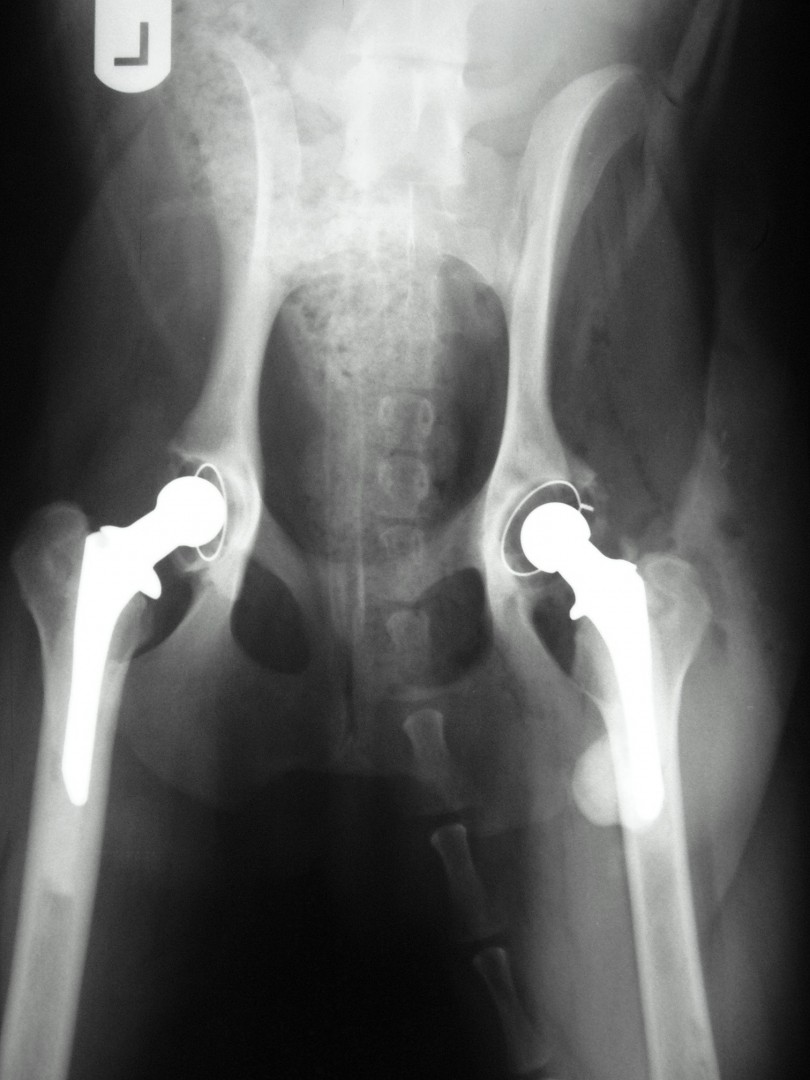

Teljes csípőízületi protézis

Bár a csípőízület megbetegedéseiről – mint a leggyakrabban tárgyalt ortopédiai megbetegedésről- első körben nem szerettem volna szólni, mégis megteszem, mert 2010. májusában egy hosszabb egyeztetést és szervezést követően beültettük az első teljes csípőízületi protézist…

Az első műtét remekül sikerült és Connor, a skót juhász kutya megkapta a bal oldali új csípőízületét. A 7 napi kórházi tartás is problémamentesen zajlott és a varratszedés idejére a műtött végtag terhelése gyakorlatilag hibátlan volt. Az 1 hónapos és a 3 hónapos kontroll RTG vizsgálatokon sem jelentkezett szövődményre utaló jel, az 1 éves postoperatív időszakban már csak az látszott, hogy a műtött lábát jobban terheli, mint a nem operált végtagot. Így 2011. júniusában – immár sokadik csípőízületi protézis műtétként- a jobb oldali csípőízületét is megoperáltuk. Connor gyakorlatilag azóta teljes életet él és vidáman játszik társaival, még birkákat is terel…A majd két éves, a protetizálás során szerzett tapasztalatok azonban nálunk is hozzák a szakirodalomban leírt szövődményi lehetőségeket és arányokat. Leggyakrabban a beültetett protézis ficamával találkoztunk, de akadt sajnos kilökődési reakció is. Ezen problémák – az előzetes tájékoztatás ellenére is- mindig váratlanul érik a tulajdonost és az állatorvost egyaránt. Megoldásuk szinte kizárólag műtéti, ami újabb kockázatot, újabb fizikai és anyagi áldozatot jelent.